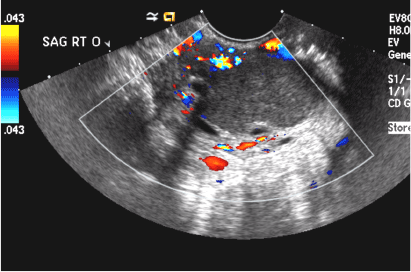

(B) Hemorrhagic cyst CORRECT

This type of cyst is well circumscribed and hypoechoic, with posterior acoustic enhancement and demonstrates a lacy reticular pattern of internal echoes due to fibrin strands (long arrow). The internal echoes also may be solid appearing with concave margins (short arrow) due to retractile hemorrhagic clot.1 The absence of internal vascular flow on color Doppler helps differentiate it from the solid components seen in ovarian neoplasm.

Hemorrhagic cysts. (A) Transvaginal pelvic ultrasound of the left ovary demonstrates a well-circumscribed hypoechoic cyst with posterior acoustic enhancement and demonstrates a lacy reticular pattern of internal echoes (long arrow). (B) Transvaginal pelvic ultrasound of the right ovary demonstrates a well-circumscribed hypoechoic cyst with solid appearing retractile hemorrhagic clot with concave margins (short arrow) and no vascular flow on color Doppler.